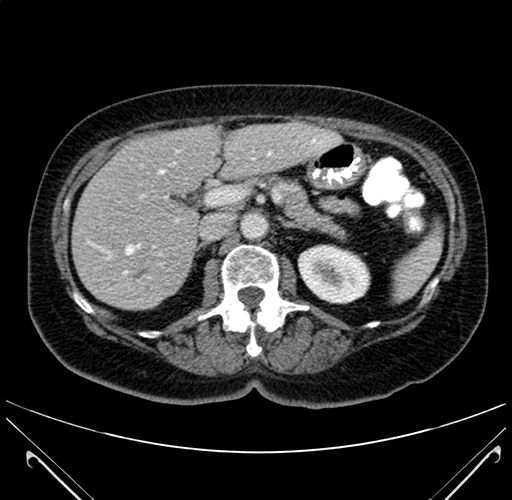

Pre-Chemo: Axial Venous